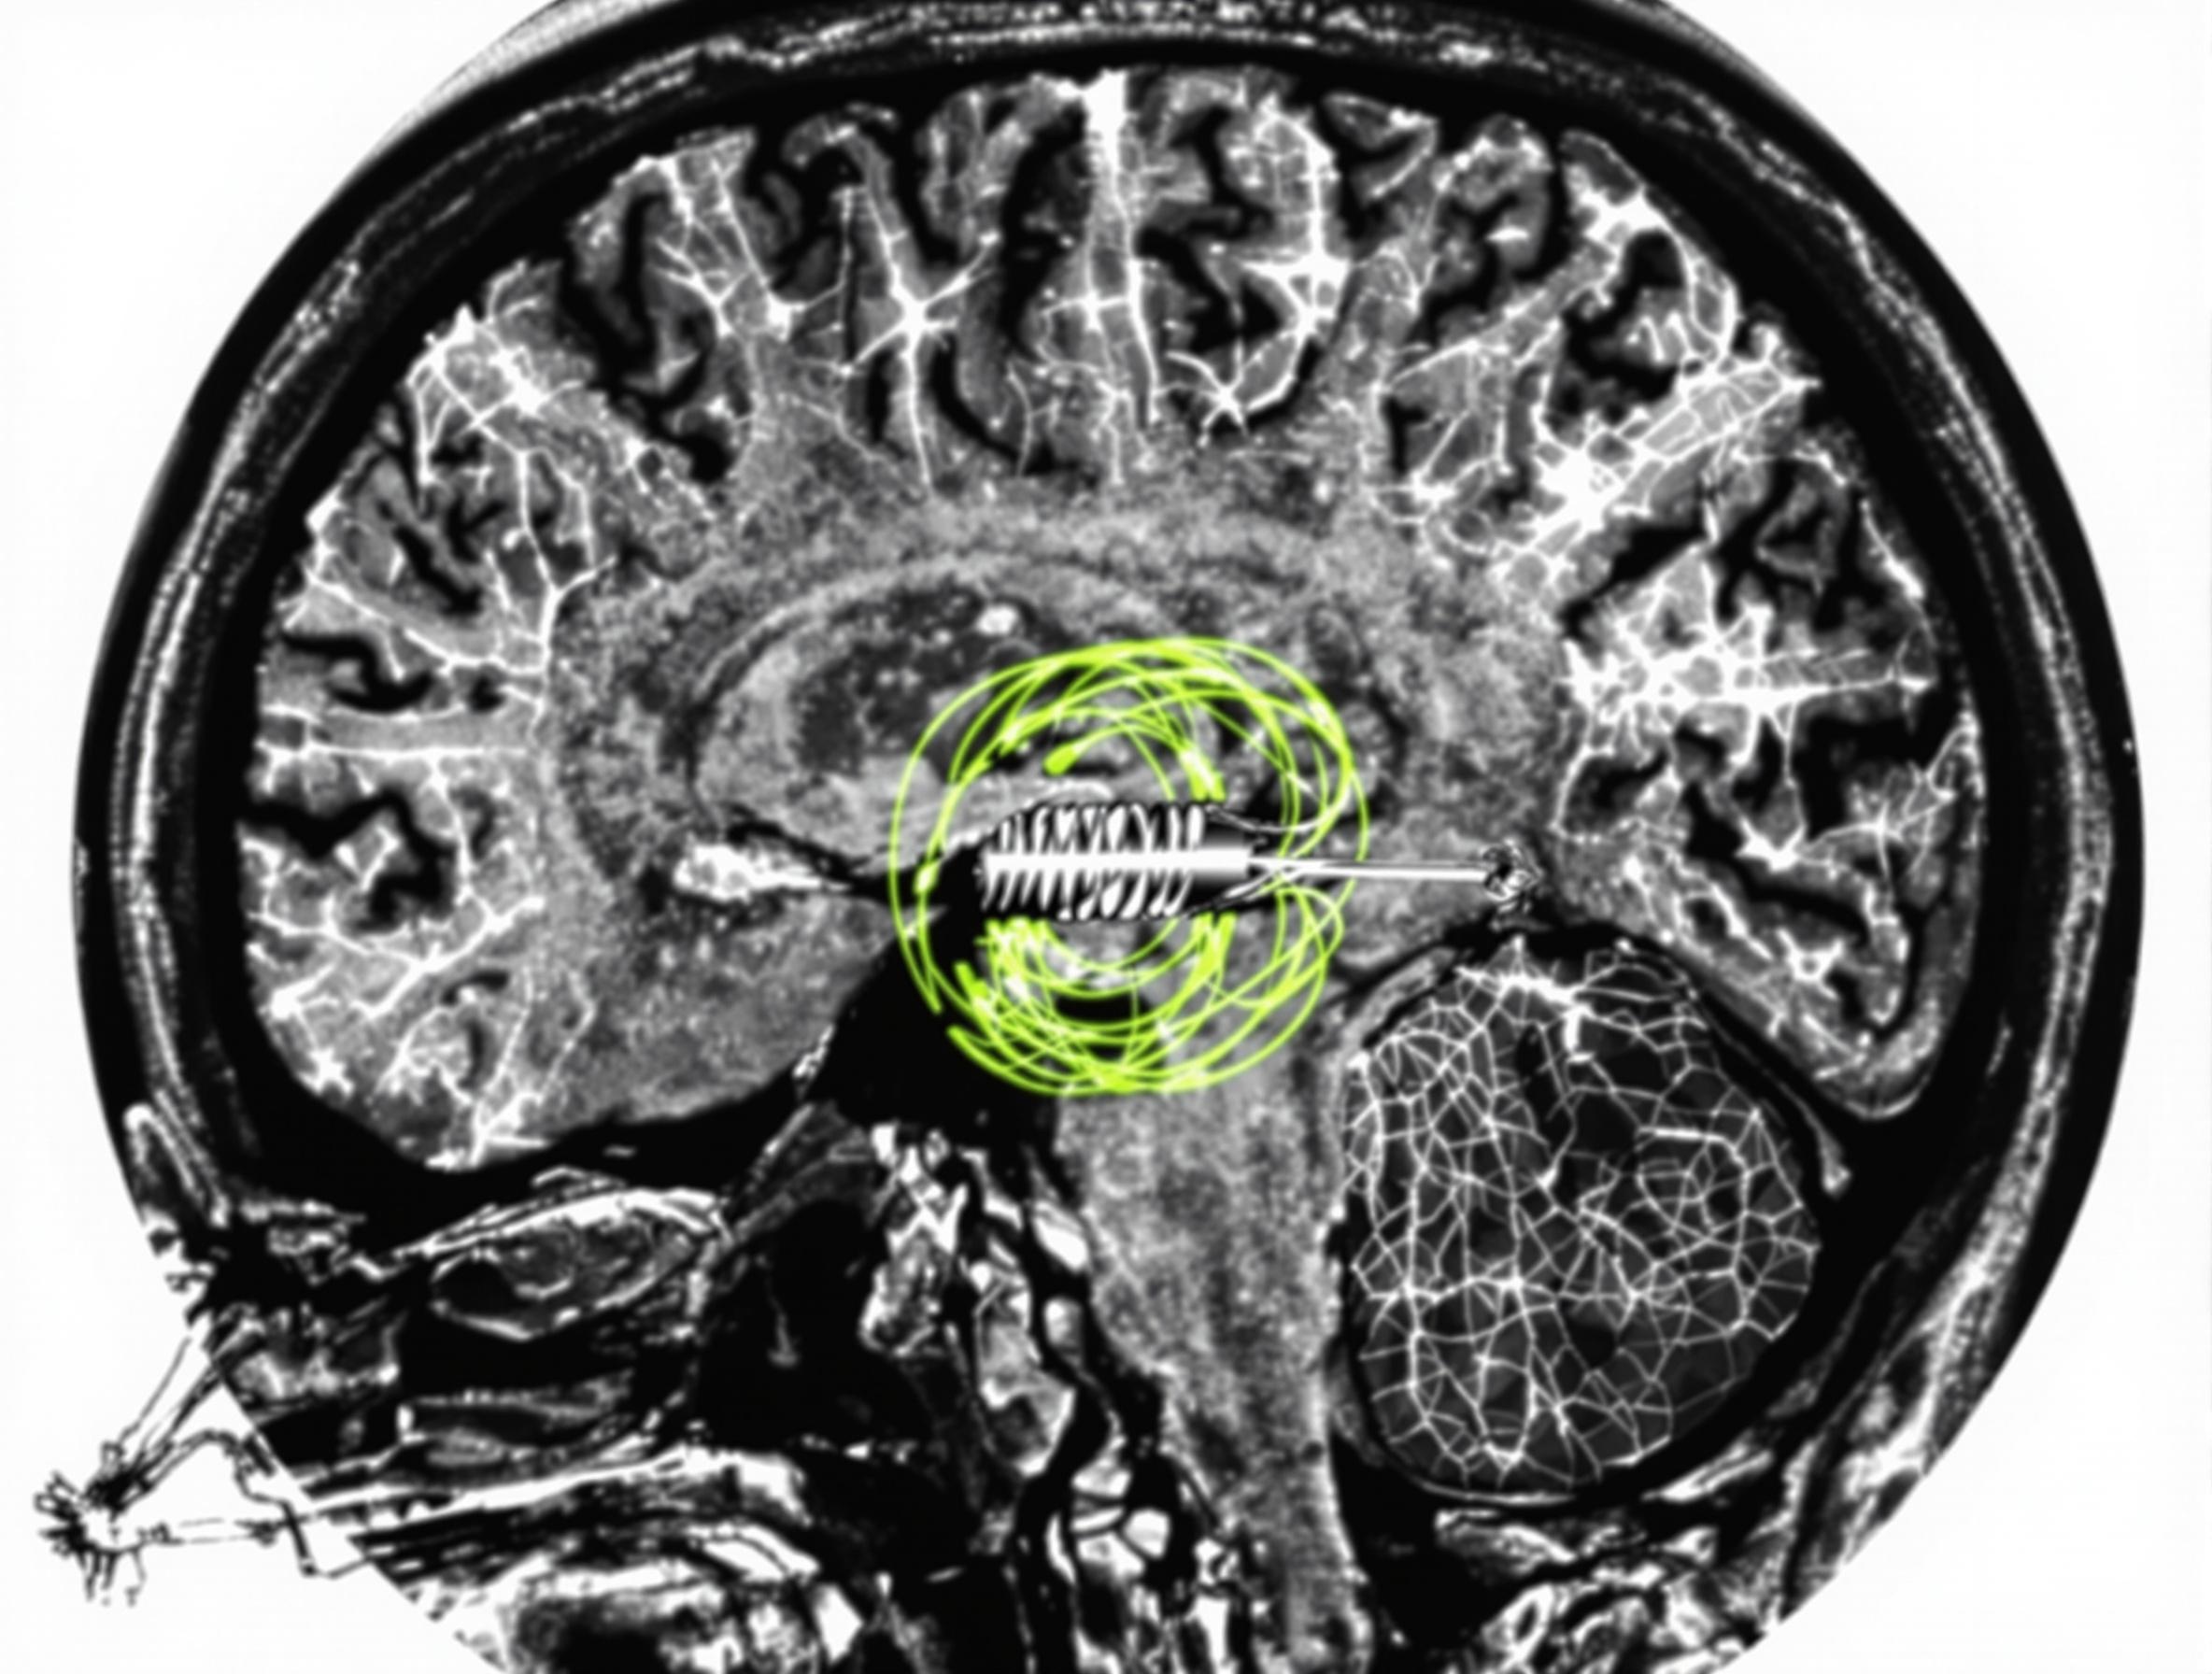

Le coiling (embolisation endovasculaire)

Le coiling, c’est le royaume de la neuroradiologie interventionnelle moderne. Oubliez les images spectaculaires de scalpels : ici, tout se joue à travers un microcathéter glissé dans vos artères, guidé sous contrôle radiologique millimétrique. Le but ? Atteindre l’anévrisme sans ouvrir la boîte crânienne (!!). Une fois le microcathéter en place dans la poche anévrismale, un coil — une spire en alliage métallique à mémoire de forme — est lâché à l’intérieur. Plusieurs coils sont souvent nécessaires pour remplir et isoler l’anévrisme du flux sanguin.

- Imagerie avancée : IRM cérébrale et/ou angio-IRM pour cartographier la topographie exacte de l’anévrisme (taille, collet, éventuelles branches à risque). Chez certains patients, un scanner injecté (CT) peut compléter le dossier.

- Angiographie cérébrale : Gold standard pour les anévrismes complexes ; permet de simuler la stratégie opératoire sous contrôle dynamique.

- Navigation sous radioscopie continue : Progression millimétrée des microcathéters jusqu’à la poche anévrismale ; injection répétée de produit iodé pour vérifier le trajet.

- Occlusion ciblée : Déploiement des coils métalliques ou du clip selon indication ; contrôle du flux sanguin en temps réel.

- Contrôle angiographique final : Vérification immédiate de l’exclusion complète de l’anévrisme sans effraction sur les branches essentielles ; passage obligée pour valider le geste !